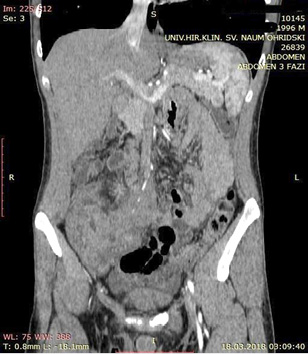

A contrast enhanced CT scan was indicated due to the palpable abdominal tumor and it revealed a formation that originates from the ileal mesentery involving the ileocolic artery and a part of the ileum with ileal wall thickening and partial obstruction (Figures 2, 3 and 4).

24.jpg Figure 2 23.jpg Figure 3

25.jpg Figure 4